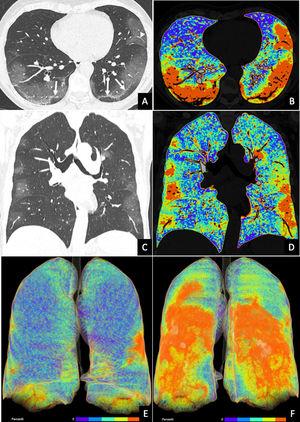

Asimismo, comenta que la principal diferencia visual de hallazgos que se ven en los exámenes de tomografía entre un paciente Covid-19 y otro que tenga una neumonía viral por otro agente viral, es la presencia de “opacidades en vidrio esmerilado” que se pueden observar en la periferia de ambos pulmones, con varios focos. Un patrón imagenológico que Felipe Allende describe como “bastante particular y característico en los pacientes con neumonia por Covid”.